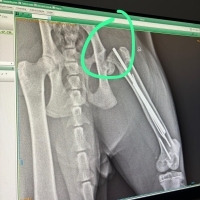

Kedimi sahiplenmeden önce, eski sahibi onu sokakta bacağı kırık şekilde bulmuş. durumu olmadığı için belediyede ameliyat etmişler ve pin takılmış. Biz 4 ay önce sahiplendik, dün pin takılan bacağı tekrar kırıldı çünkü önceki ameliyat berbat yapılmış. Yeni ameliyatta femur başı çıkarıldı, sorunlu pin çıkarıldı. Ancak veteriner hekim biraz olumsuz konuştu sinirler batan pinden zarar gördü bu bacağını kullanır mı kullanmaz mı net konuşmadı 1 ay kafes tedavisi görecek evde ayrıca çok ödem olduğu için kortizon tedavisi gerekebilir. His kaybı yaşamasından ve bacağını kaybetmesinden korkuyorum, aynı durumu yaşayan var mı ?